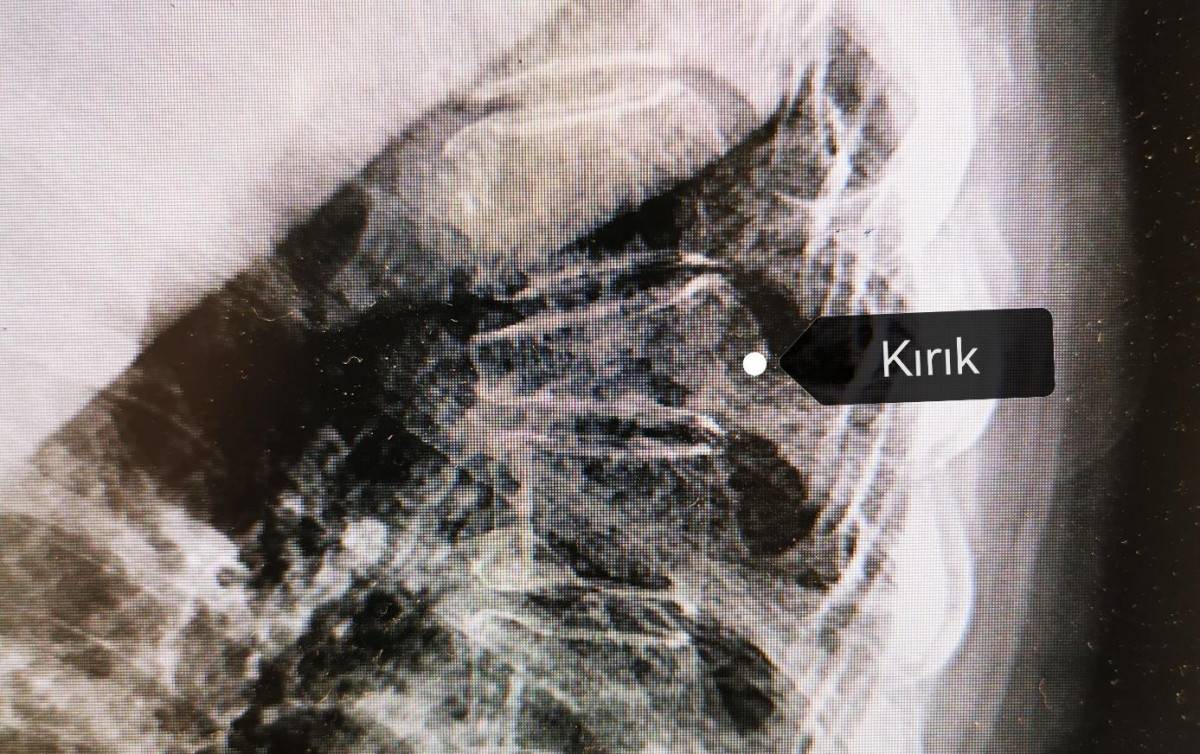

Kemik erimesi; kırıklara, sakatlıklara ve yaşam kalitesinin azalmasına neden olan; kemiğin içini boşaltıp kalitesini bozduğu için kırık olana kadar bulgu vermeyen, bu yüzden de “sessiz hırsız” olarak adlandırılan bir hastalıktır.

Osteoporoza bağlı kırıklar genellikle kalçada, bileklerde ve omurgada görülür. Kalça kırıkları çoğunlukla ameliyat gerektirirken, bilek kırıkları alçı tedavisinin yetersiz kaldığı durumlarda cerrahi müdahale gerektirebilir.

Yaşlılarda en sık görülen kırıklar; omurga, bilek ve kalça kırıklarıdır. Kemiklerin zayıflaması, omurlarda kompresyon (çökme) kırıklarına yol açabilir. Bu çökme kırıkları zamanla omurganın gücünü ve şeklini değiştirerek kronik sırt ağrısına, kamburluğa veya boy kısalmasına neden olabilir.